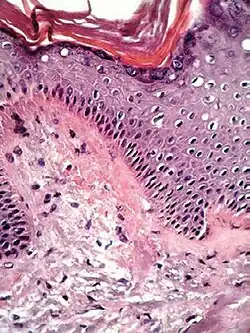

Spongiotic dermatitis

It is characterized by epithelial intercellular edema.[2]

| Generally/Not otherwise specified[notes 2] | Typical findings:[2]

Typical findings:[2]

PAS stain is essential to exclude fungal infection.[2] |